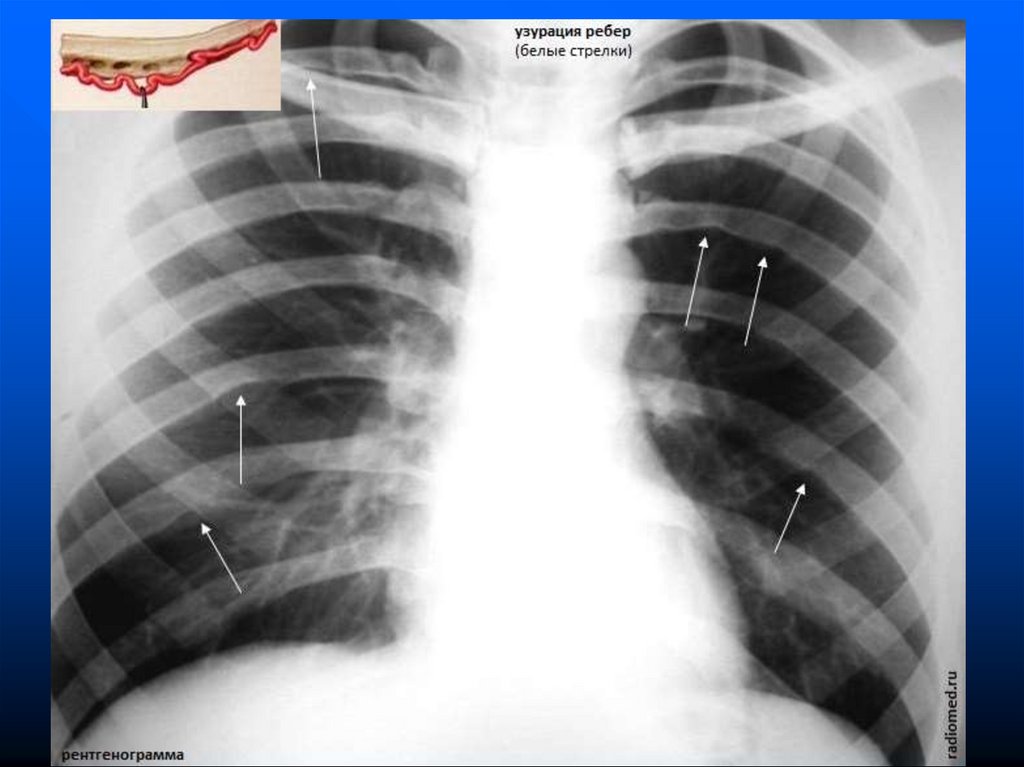

внутриутробные

аномалии сердечно-сосудистой